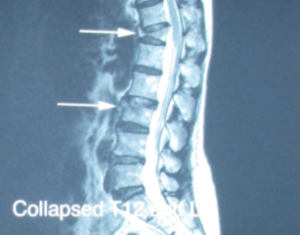

到今年4月,關女士又因雙腳乏力再一次跌倒,照了X-光並沒有看到脊椎有新骨折,但之前的胸椎第12節開始有下陷及前傾的現象,這次醫生也只是給她止痛消炎藥並囑咐她回家多休息。之後關女士發覺腰痛一天比一天嚴重,無論坐着、行走、站立都無法紓緩腰痛的情況,就算服食了藥物也不能止痛。病人5月來見筆者,由於她的病史及徵狀看來是因雙腳乏力跌倒,加上病人本身患有骨質疏鬆症而使她跌倒後脊椎骨折,經詳細檢查後決定以磁力共振作頸椎、胸椎及腰椎掃描。結果發現病人的胸椎第12節及腰椎第3節骨折,胸椎12節尤其嚴重,出現下陷、前傾,亦有輕微壓向中樞神經的現象(見圖―)。嚴重的骨折令關女士的腰痛日漸加劇,筆者把病人轉介至神經外科醫生處進行針孔微創椎體成形術(Vertebroplasty)。關女士完成了這項小手術後,困擾她多時的腰痛幾乎全消失了。

圖―

胸椎12節尤其嚴重,出現下陷、前傾,亦有輕微壓向中樞神經的現象。

圖四

胸椎12節及腰椎第3節骨折完 成椎體成形術